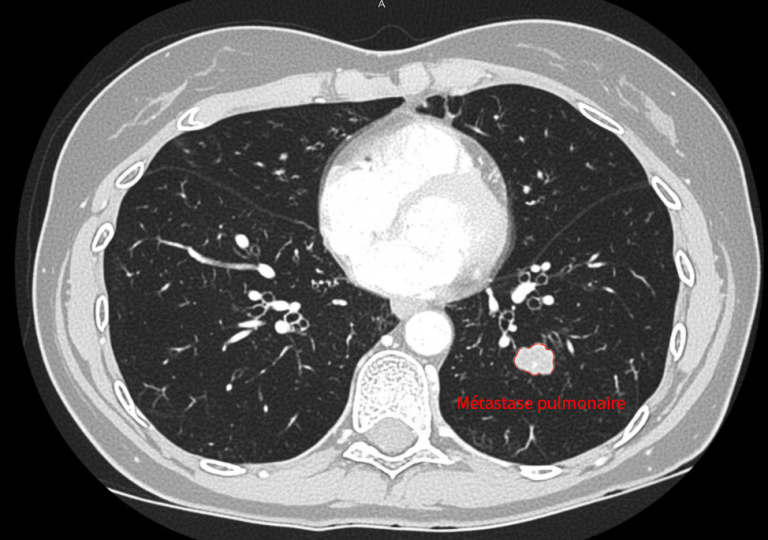

• une métastase pulmonaire de 2,5 cm, située près de structures centrales,

Traitement pulmonaire par cryoablation

La lésion pulmonaire est traitée par cryothérapie, permettant une destruction efficace tout en évitant une chirurgie lourde (lobectomie).

Le contrôle à distance montre une réponse complète des lésions, sans nouvelle métastase, permettant la poursuite d’une simple surveillance.

En images

Images du traitement des organes (poumon et foie) avant, pendant et après le traitement.